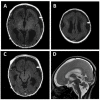

Tubulin proteins play a role in the cortical development. Mutations in the tubulin genes affect patients with brain malformations. The present report describes two cases of developmental and epileptic encephalopathy (DEE) due to tubulinopathy. Case 1, a 23-year-old boy, was found to have a brain malformation with moderate ventriculomegaly prenatally. Hypotonia was noted at birth. Seizures were noted on the 1st day with multifocal discharges on the EEGs, which became intractable to many anticonvulsants. Brain MRI showed marked dilated ventricles and pachy/polymicrogyri. He became a victim of DEE. A de novo mutation in TUBB2B was proven through next-generation sequencing (NGS). Case 2, a mature male baby, began to have myoclonic jerks of his limbs 4 h after birth. EEG showed focal sharp waves from central and temporal regions. Brain MRI showed lissencephaly, type I. The seizures were refractory initially. A de novo mutation in TUBA1A was proven at the 6th week through NGS. He showed the picture of DEE at 1 year and 2 months of age. The clinical features of the tubulinopathies include motor delay, intellectual disabilities, epilepsy, and other deficits. Our cases demonstrated the severe form of tubulinopathy due to major tubulin gene mutations. NGS makes the early identification of genetic etiology possible for clinical evaluation.